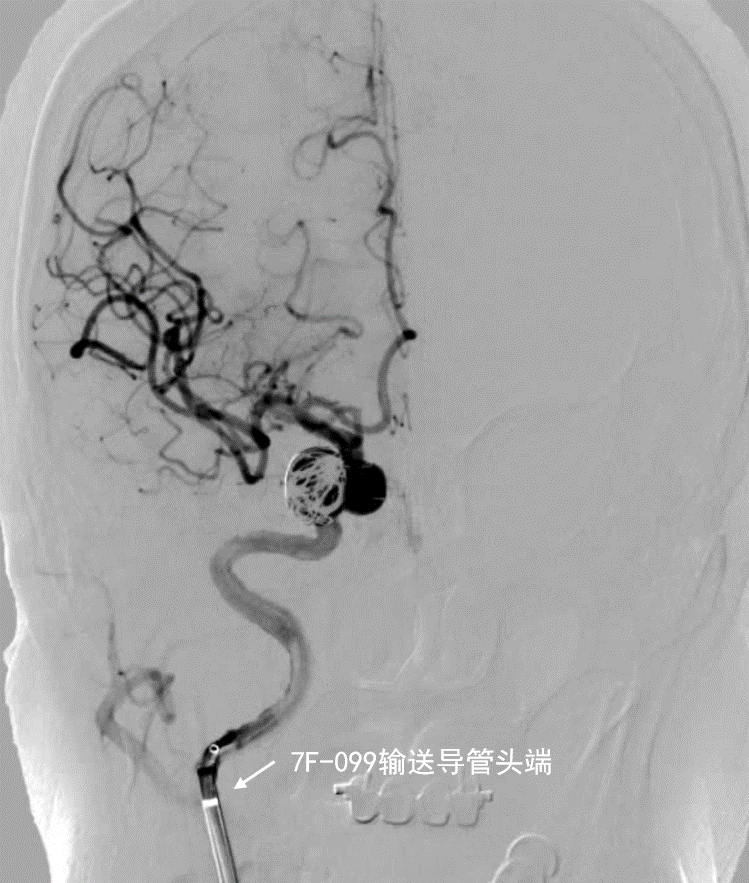

- 第一枚血流导向密网支架释放后造影

深瑞达7F输送导管正位造影

深瑞达7F输送导管侧位造影